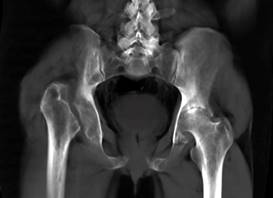

A la exploración física: postura con acortamiento de extremidad pélvica derecha, con escoliosis izquierda compensatoria. Masa ósea a la palpación correspondiendo al trocánter mayor 5 cm por arriba de la altura del contralateral. Arcos de movimiento bloqueados en la derecha, la rotación interna es limitada por dolor en cadera izquierda, el resto de exploración normal. La tomografía de cadera (Figuras 1 y 2) mostró desaparición de cabeza y cuello femoral derecho y elevación del trocánter mayor por luxación, en cadera izquierda se encontró coxartrosis severa. Se diagnosticó síndrome de Gorham-Stout, con resultados normales de laboratorio; se procedió a biopsia, la cual confirmó diagnóstico (Figura 3). Se canalizó a traumatología para colocación de prótesis bilateral.

Figura 1: Imagen de tomografía computarizada de pelvis, en la cual se muestra ausencia de cabeza y cuello femoral derecho, con desplazamiento superior por luxación del fémur 5 cm por arriba de la altura del trocánter contralateral. La cadera izquierda con disminución del espacio articular, presencia de esclerosis, quistes subcondrales y osteofitos por coxartrosis izquierda severa.